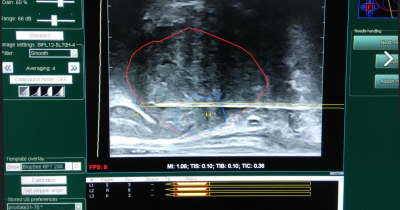

ΔΕΙΤΕ ΝΕΑ ΓΙΑ ΤΗΝ FUSION ΒΙΟΨΙΑ ΠΡΟΣΤΑΤΗ

ΔΕΙΤΕ ΤΑ ΣΗΜΑΝΤΙΚΑ ΠΛΕΟΝΕΚΤΗΜΑΤΑ ΤΗΣ FUSION ΒΙΟΨΙΑΣ ΠΡΟΣΤΑΤΗ ΜΕ ΤΟΠΙΚΗ ΑΝΑΙΣΘΗΣΙΑ

ΚΛΕΙΣΤΕ ΤΩΡΑ ΡΑΝΤΕΒΟΥ ΓΙΑ FUSION ΒΙΟΨΙΑ ΠΡΟΣΤΑΤΗ